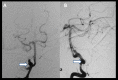

Case report: We report an 11-year- old boy with left atrial myxoma and multiple cerebral oncotic aneurysms. The characteristics of these aneurysms are indefinite and variable. The "Metastasize and Infiltrate" theory may be the key mechanism in the formation of these aneurysms.

Conclusions: Magnetic resonance imaging (MRI), computed tomography (CT) and angiography are useful in the diagnostics while digital subtraction angiography (DSA) is the best option. There are no definite guidelines for therapy of these aneurysms. Resection of cardiac myxomas, chemotherapy, radiotherapy, coil embolization and surgical treatment could be helpful.